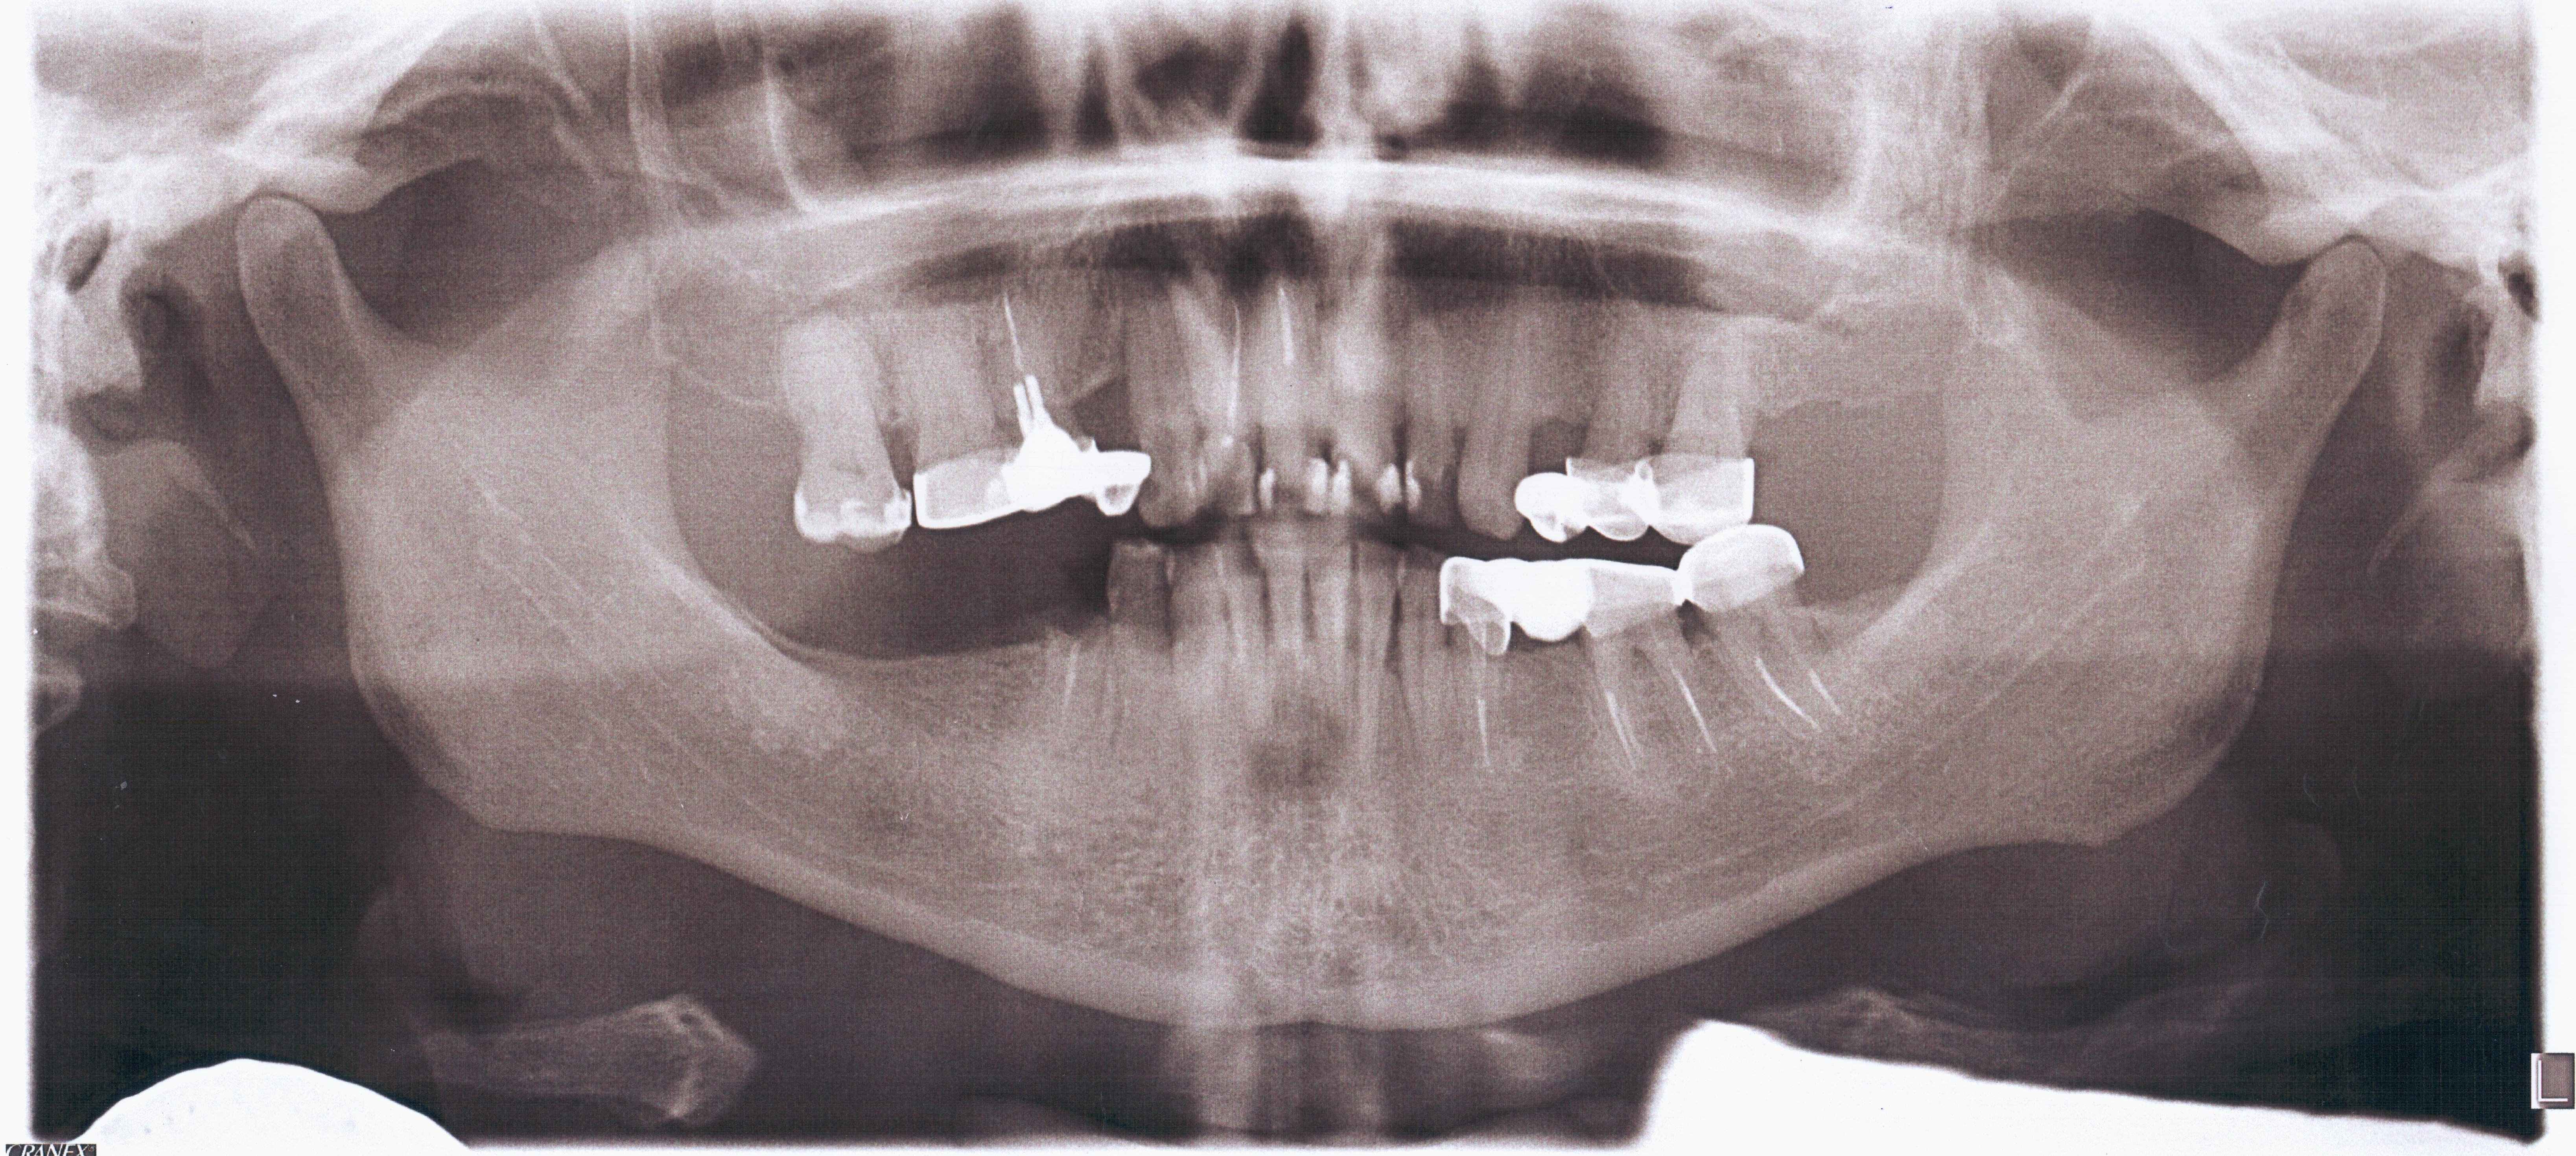

Orthopantomography (Fig 2) showed a minor area of ​​alveolar ridge resorption in the area between the lower left lateral incisor and canine.